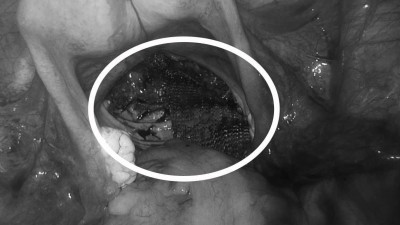

Врачи Наро-Фоминской больницы спасли 40-летнюю пациентку с серьезным осложнениям после травмы позвоночника.